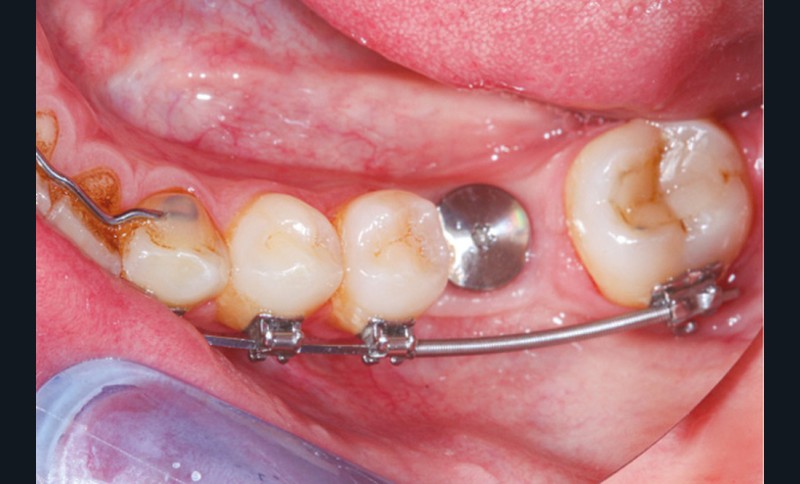

La prise en charge de ces édentements nécessite un examen complet du site implantaire et de l’environnement [16]. Les conséquences du non-remplacement rapide que nous venons d’énumérer sont à prendre en compte et à corriger pour une intégration optimale de la restauration prothétique implantaire. Ainsi, des corrections orthodontiques peuvent être nécessaires avant ou pendant la thérapeutique implantaire.

Le temps de l’ostéointégration, des versions ou migrations sont aussi possibles et le recours à des dispositifs de maintien de l’espace peut se révéler indispensable (fig. 22 et 23).